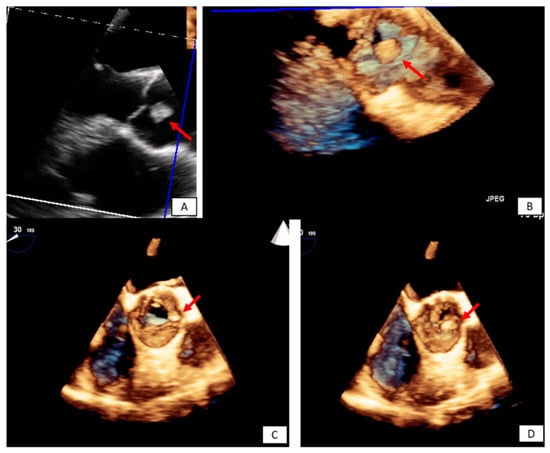

3.2. Transesophageal Echocardiography

- Strachinaru, M.; Damry, N.; Duttmann, R.; Wauthy, P.; Catez, E.; Lutea, M.; Costescu, I.; Morissens, M. Ultrasound Contrast Quantification for the Diagnosis of Intracardiac Masses. JACC Cardiovasc. Imaging 2016, 9, 747–750. [Google Scholar] [CrossRef] [PubMed]

- Zaragosa-Macias, E.; Chen, M.A.; Gill, E.A. Real time three-dimensional echocardiography evaluation of intracardiac masses. Echocardiography 2012, 29, 207–219. [Google Scholar] [CrossRef] [PubMed]